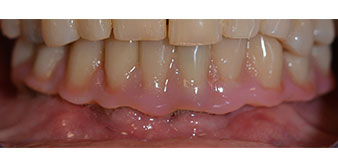

The impression and bite registration were then performed so that the dental technician could begin producing the provisional restoration immediately. This was then screwed in on the same day (Fig. 17 and 18).

Following the time required for the osseointegration, the final impression of the implants could be performed and the final denture produced accordingly (Fig. 19 and 20). At this point, the dentist and patient were able to decide together whether to use a ceramic or acrylic veneer and a zirconium or metal framework. In this case, Dr. Pascu’s team decided on an acrylic veneer based on the unclear prognosis for the maxillary dentition and the fact that tooth 24 is elongated. This type of veneer is generally considerably easier to adapt and can thus be subsequently altered to reflect the new situation in the maxilla.

Osseointegration

Implants